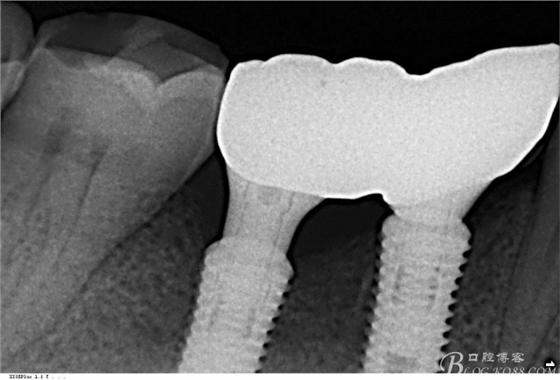

因?yàn)樽笊献鲞^(guò)種植,口內(nèi)見(jiàn)

C6頰側(cè)骨缺損凹陷,對(duì)合金屬全冠,

三維檢查種植體位置,方向,平行度